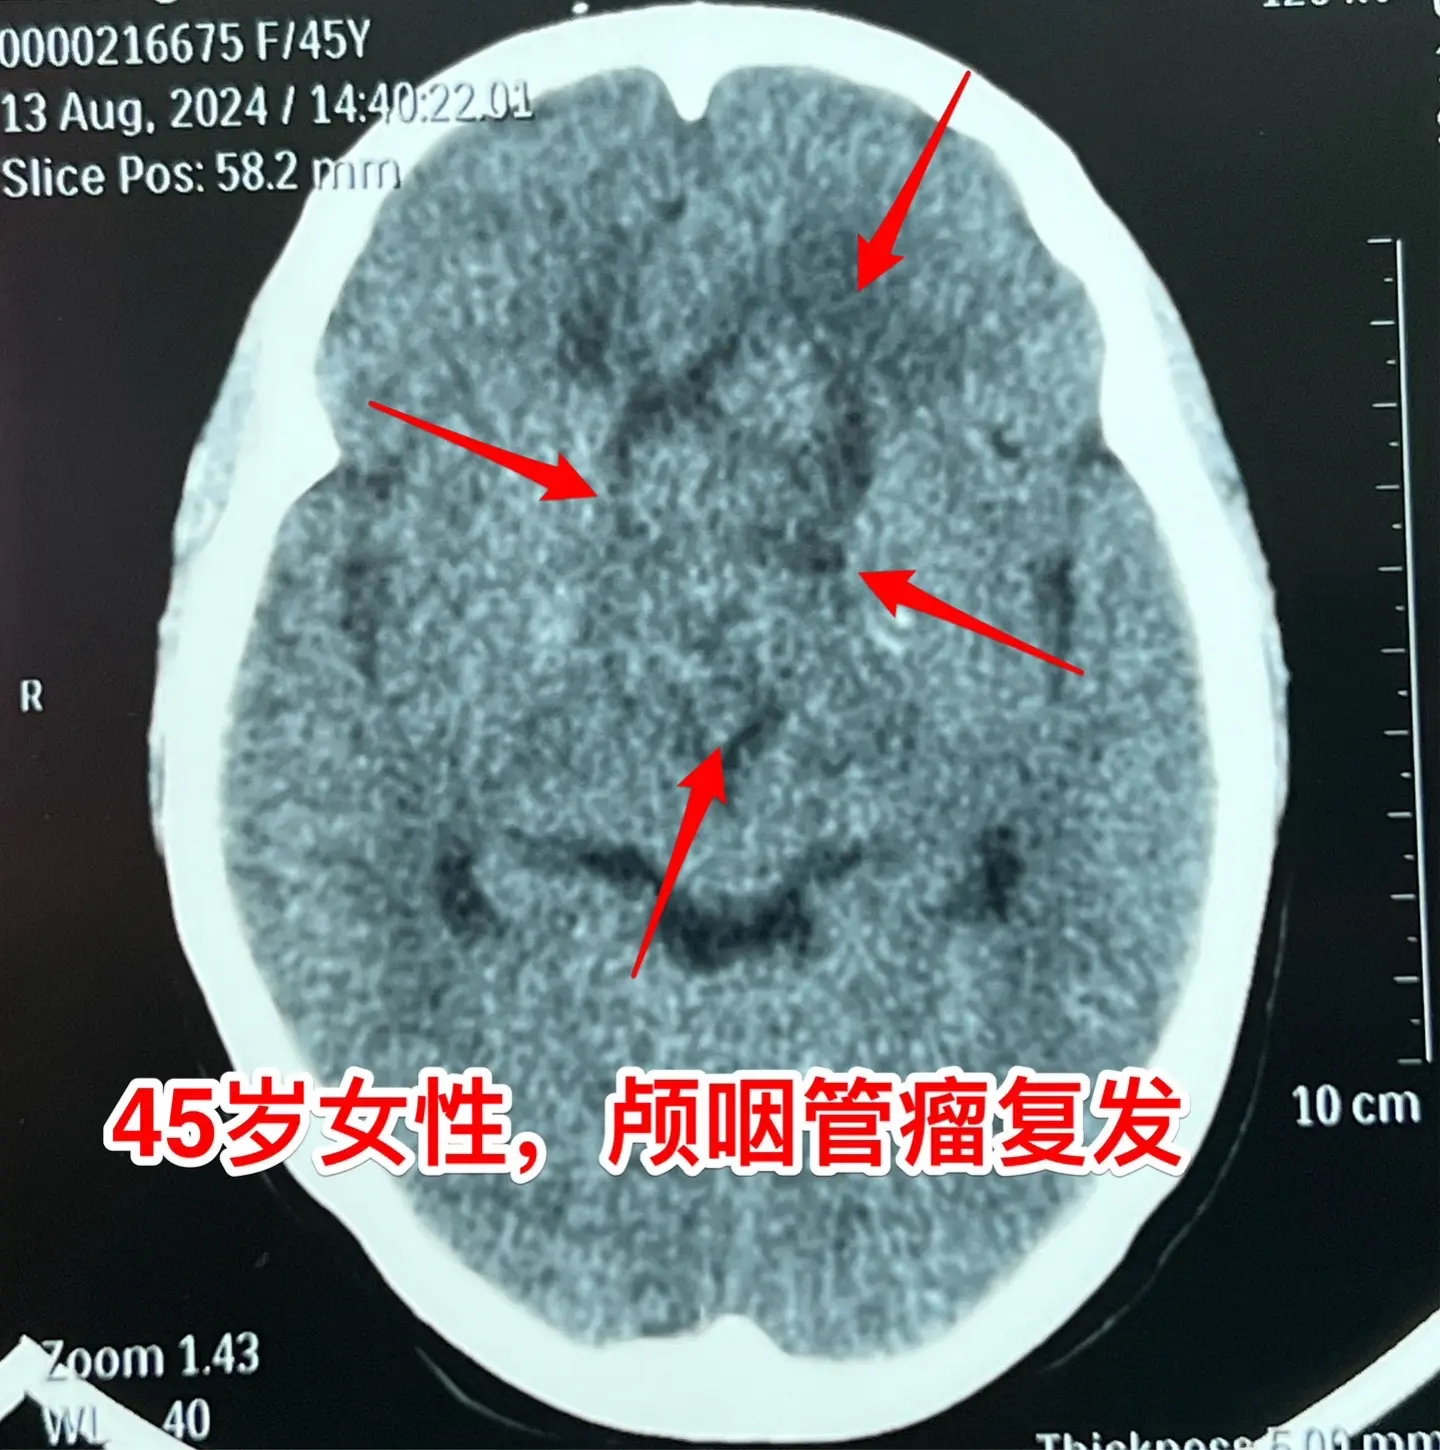

巨大的颅咽管瘤。45岁浙江女性,在外院作了颅咽管瘤手术不到一年,作磁共振显示肿瘤复发,而且体积巨大。 病人视力很差,记忆力也差,精神不好。 这么大的颅咽管瘤一般是需要作手术的。显而易见是这样的手术是很有难度的,很考验医生的技术和能力! 从影像学资料可以看出,这是乳头型颅咽管瘤。如果害怕作手术,对于运气好、经济状况好的病人,也可以试一试靶向药,也许有效。 这个病人选择了作手术!8月16日我们经过九个小时的紧张奋战,将肿瘤完全切除了。手术后CT结果很好。